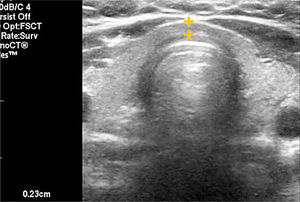

EL TIROIDES NORMAL Y PATOLÓGICOEl tiroides normal al ultrasonido tiene la forma de una letra H (para otros como mariposa), con lóbulos derecho e izquierdo con predominio franco del eje cráneo caudal, algunos más y otros menos estilizados, de contornos lisos, de bordes más bien agudos, generalmente entre 30 y 60mm de eje longitudinal según la literatura (entre 30 y 42mm en mi experiencia) (Figura 1). El istmo también con predominio del eje longitudinal, con un diámetro anteroposterior no mayor a

3mm (Figura 2). La presencia del lóbulo piramidal no es rara, alrededor del 20%11, siendo dependiente la mayoría de las veces del istmo y las otras veces del borde medial del lóbulo izquierdo (Figura 3).